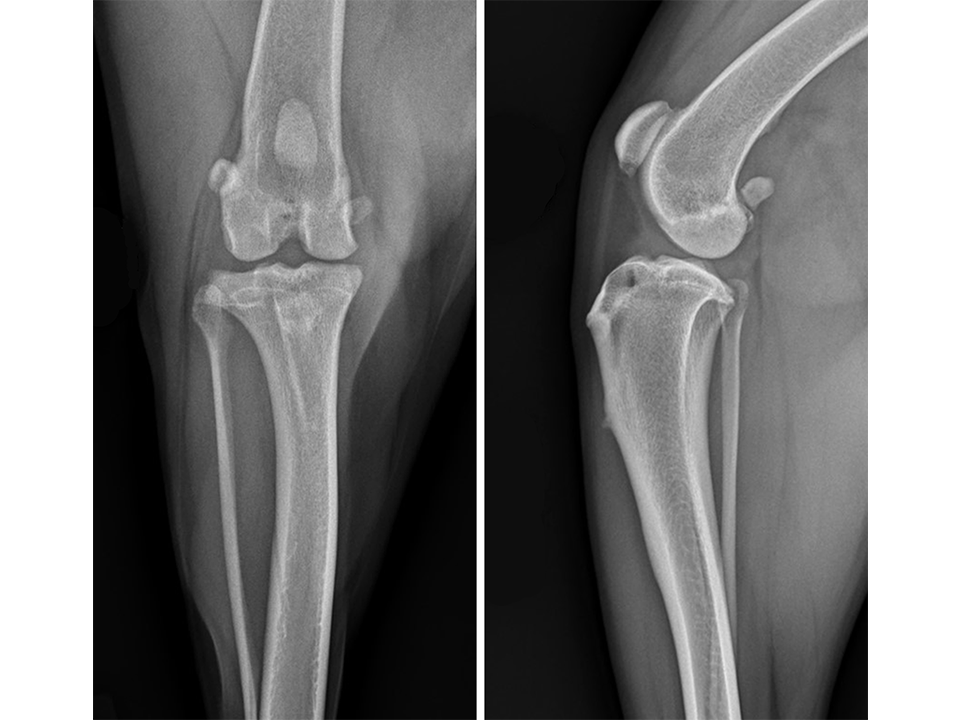

Immediate postoperative radiographs (Fig 7) revealed satisfactory implant and osteotomy positioning. Radiographs obtained 10 weeks postoperatively (Fig 8) showed no evidence of implant-associated complications and partial bone healing within the osteotomy gap. Osteoarthritic changes within the joint were static. Clinically at this stage, mild bilateral pelvic limb lameness was apparent bilateral stifle joint effusion. The left stifle joint was stable in CrTT with no pain response upon stifle joint manipulation.

The patient presented again 11 months postoperatively for assessment of right pelvic limb lameness associated with CrCL rupture. At this stage severe right pelvic limb lameness was evident but no lameness of the left pelvic limb was observed. While the right stifle joint was unstable in cranial drawer and CrTT, the left stifle remained stable with no pain response upon palpation over the implants and a normal range of motion of the joint. Radiographs of the previously operated left stifle (Fig 9) revealed no implant-associated complications and healing of the osteotomy. The osteoarthritic changes were static radiographically. TTA was performed on the right tibia at this time using a 13.5 mm wedge and a size 6 plate as had been used on the left previously.